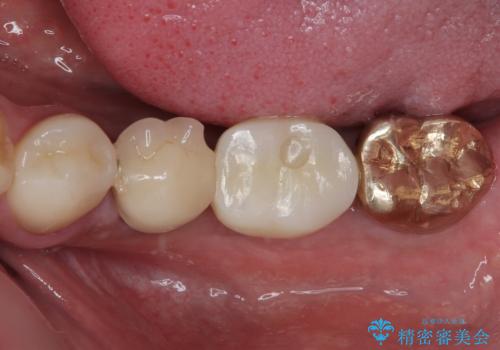

インプラント埋入時に植立具合の安定性を測定したところ、十分な数値が得られたため、速やかに仮歯を装着して咬合回復をさせることができました。

抜歯を含めた外科処置を1回に抑えることができ、あっという間に治療を終えることができました。